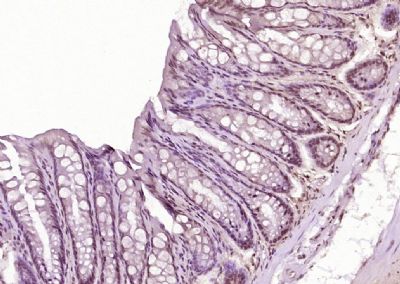

目录号:bs-7738R

商品规格:50ul